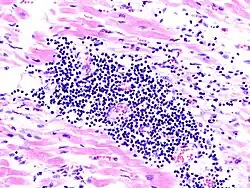

Histopathologie der viralen Myokarditis

Eine Myokarditis kann durch Bakterien, Pilze, Parasiten und Viren verursacht sein. In Europa und den USA werden in über 50 % der Fälle Enteroviren, besonders Coxsackie-Viren B1–B5, für eine Myokarditis verantwortlich gemacht. Ein ursächlicher Zusammenhang ist außerdem bei einigen Serotypen der Coxsackie-A-Viren und der ECHO-Viren erwiesen. In weiteren Fällen konnten Parvovirus B19, Adenoviren, Influenzaviren und Mumpsviren aus dem Myokard isoliert werden.